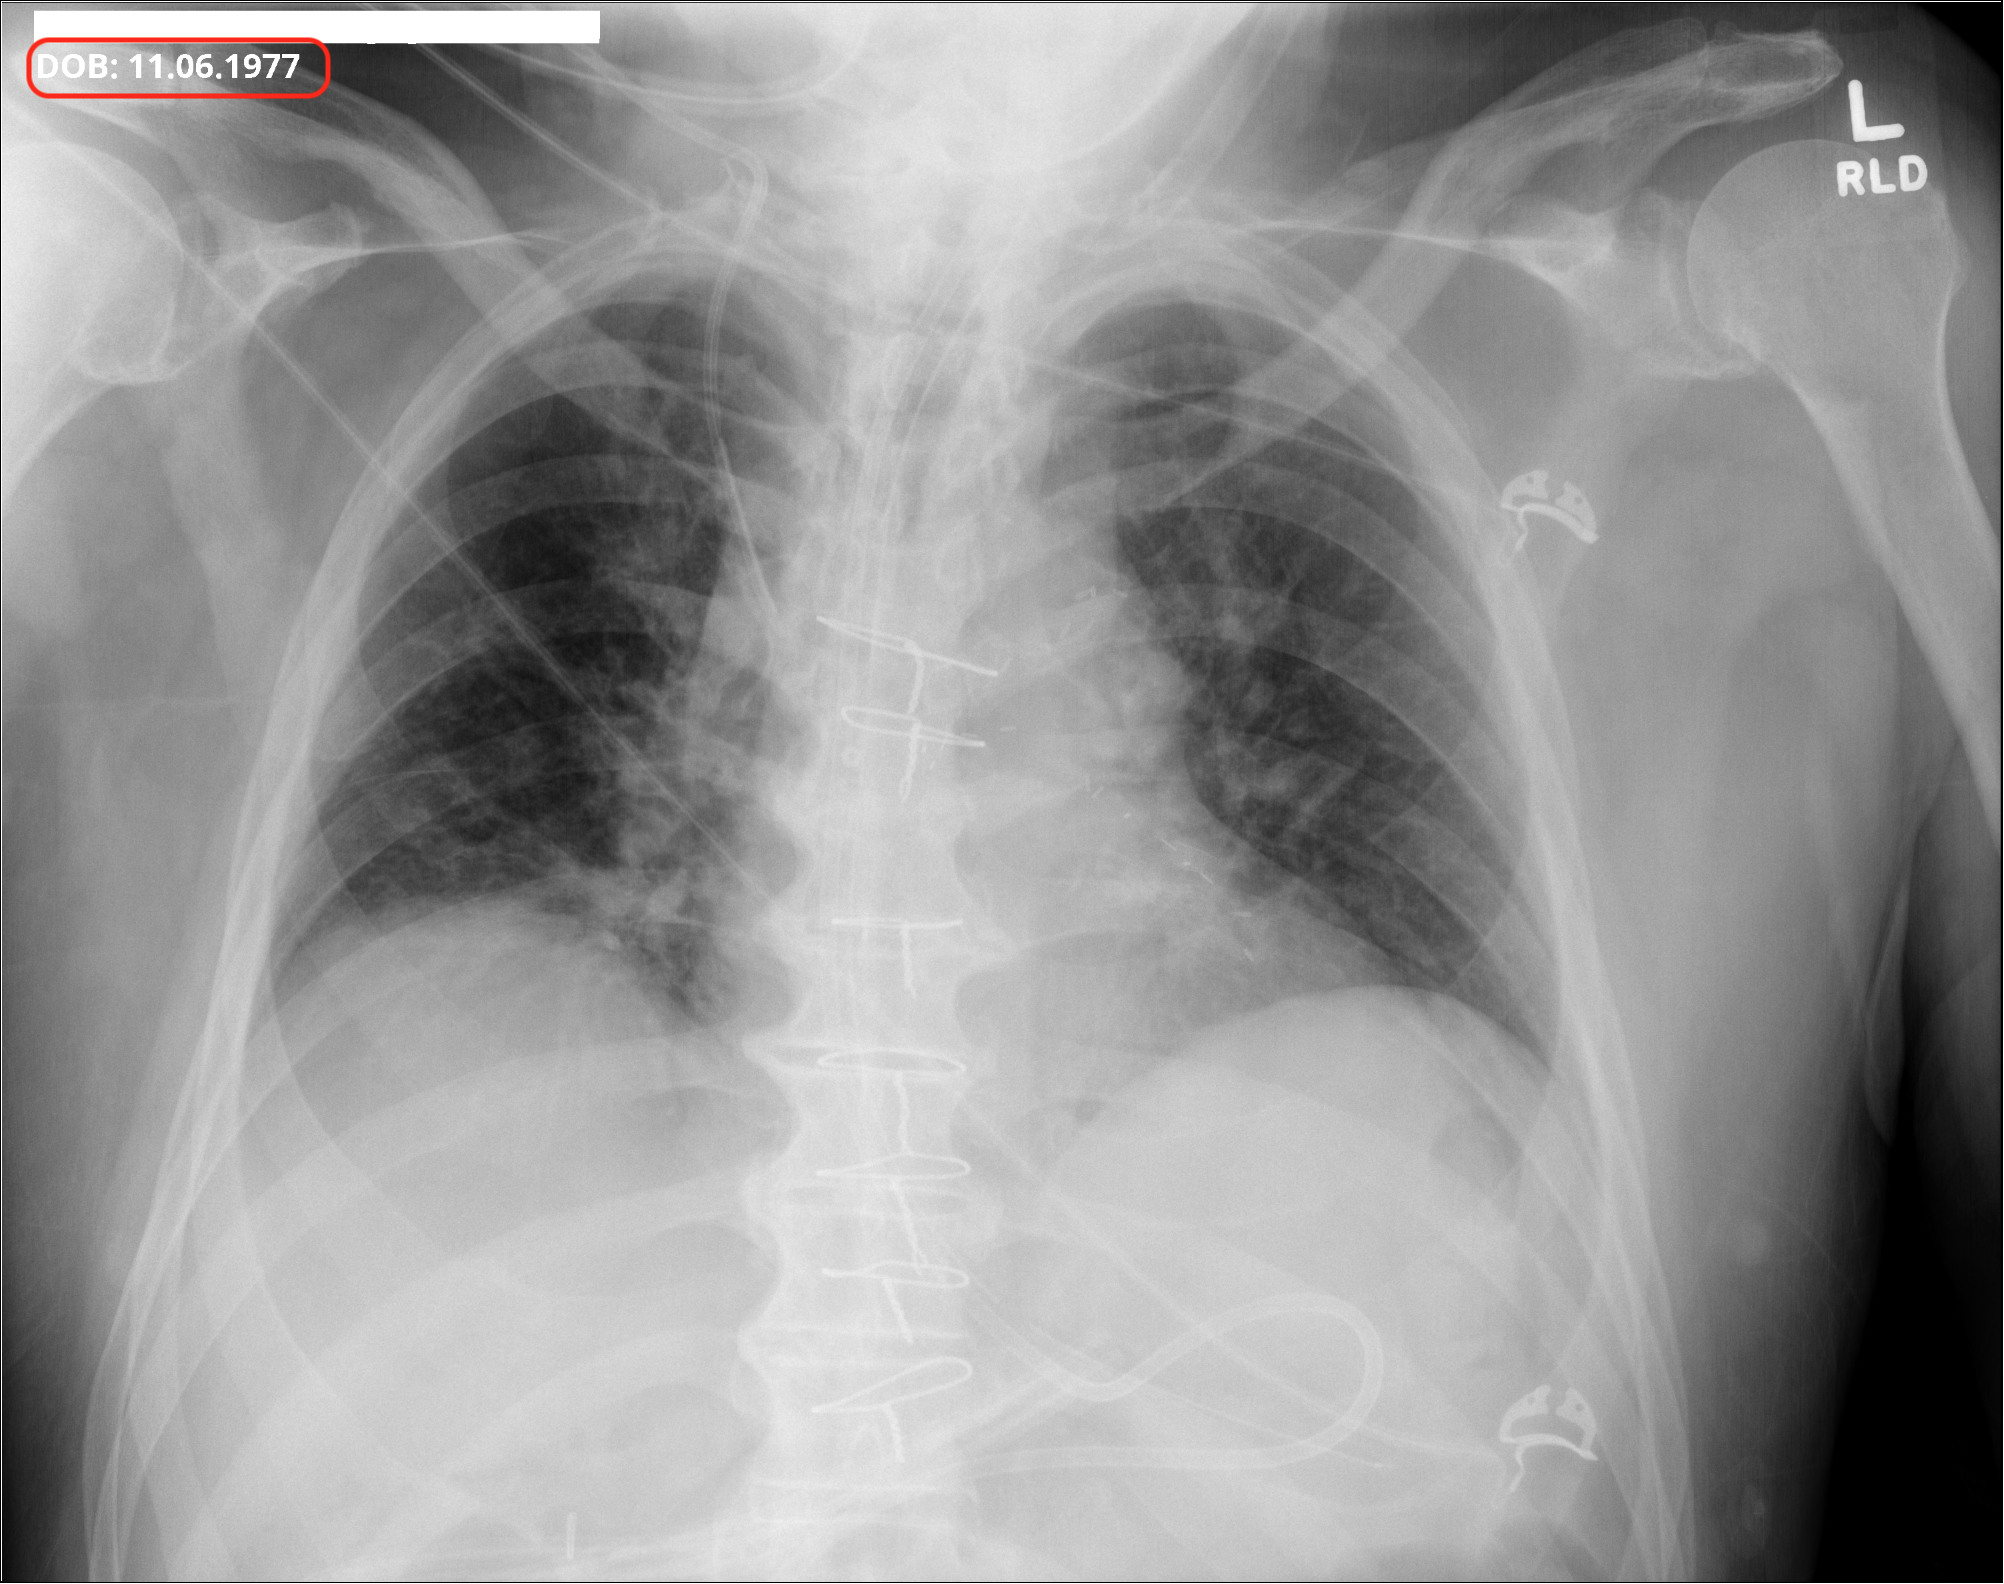

The Digital Imaging and Communications in Medicine (DICOM) standard, which is widely adopted for medical imaging, embeds patient-related information as metadata in the DICOM files. For some modalities, manufacturers embed certain PHI/PII, such as patient name and date of birth, in the pixel matrix of images, such as for ultrasound (Bidgood Jr et al., 1997; Mildenberger et al., 2002). DICOM data elements used as attributes of information objects are identified by numeric tags (group number and element number), with even-numbered group numbers representing standard attributes, and odd-numbered groups representing private attributes specific to manufacturers. In a DICOM medical image, many identifiers are stored as predefined attributes in the DICOM header. These include the Patient’s Name (0010, 0010), and Patient’s Birth Date (0010, 0030), etc. PHI/PII can be present in either such structured DICOM attributes intended for the purpose, but also in free-text fields, such as Additional Patient History (0010, 21B0). Header and pixel data of DICOM images must, therefore, be de-identified. Fiugre 1 shows a DICOM image comparison before and after deID. The well-defined structure of fixed DICOM attributes allows for semi-automatic deID to remove corresponding PHI/PII with relative reliability, but requiring verification, using tools such as The Radiological Society of North America (RSNA) Clinical Trial Processor (CTP) (Freymann et al., 2012), DICOM Library (Macdonald et al., 2024), and XNAT platform (Clunie et al., 2024). Recently, the technologies of medical image deID have evolved from strict rule-based systems to include hybrid approaches such as deep-learning-based systems for object character recognition in pixel images, and large language models (LLMs) for detection of PHI/PII within free text fields (Langlois et al., 2024; Kopchick et al., 2022). The DICOM deID process for removing sensitive information needs to follow instructions of a set of deID standards such as those in DICOM PS3.15 (National Electrical Manufacturers Association (2025), NEMA) for PHI/PII fields to remove or modify, and satisfy HIPAA DeID requirements.

4.2 Pixel deID

Improper pixel image deID may be partial, such as the retention of partial PHI/PII information or the removal of non-PHI/PII information. In the top-row of Figure 4, the deID process result contains false negatives. For example, only the last name is de-identified in the example, while the first name remains. In the bottom-row of Figure 4, the text ’SEMI-UPRIGHT’ at the position of the bottom red box has been misrecognized as PHI/PII information and then incorrectly redacted.